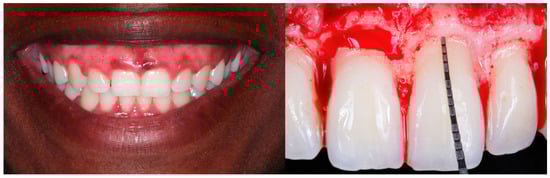

2.4. Surgical Approach and Clinical Recommendations